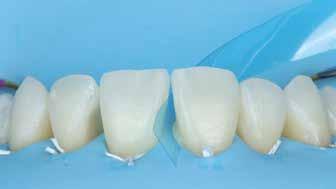

Az alábbi cikkben egy I. osztályú üreg thermo-viszkózus kompozittal, okkluzális matrica technikával történő ellátásának lépéseit ismertetjük (1. ábra). A kofferdám felhelyezését követően az okkluzális felszín anatómiai karakterisztikáját átlátszó, folyékony, fényrekötő kompozit (Clip Flow, VOCO) segítségével rögzítettük. Az anyagot egy bondecset alkalmazásával vittük fel a fog okkluzális felszínére, majd 10 másodpercen keresztül polimerizációs lámpával megvilágítottuk (2–4. ábra). A megkötött átlátszó okkluzális matrica ellenőrzését követően (5. ábra) alkoholba helyeztük (ethanol vagy izopropil-alkohol), az oxigén inhibíciós réteg eltávolítása érdekében. Ezután a szuvas foganyagot eltávolítottuk (6–7. ábra). A zománcot 30 másodpercig, a dentint pedig 15 másodpercig savaztuk (DeTrey Conditioner 36, Dentsply Sirona), majd a felszínt levegő-vízspray segítségével lemostuk (8 –10. ábra). Mivel a fogbélkamrát már csak egy vékony réteg ép dentin fedte, ezért a pulpa vitalitásának megőrzése érdekében az üreg pulpális falait védőréteggel fedtük (DeTrey Conditioner 36, Dentsply Sirona) (11. ábra). Az adhéziót Futurabond DC (VOCO) felhasználásával biztosítottuk. A bondot bondecsettel 20 másodpercen keresztül az üreg falaiba masszíroztuk, majd 5 másodpercen keresztül olajmentes levegő spray-vel megfújtuk a felesleg eltávolítása és a bondréteg elvékonyítása érdekében. A bondot ezt követően 10 másodpercen keresztül polimerizációs lámpával megvilágítottuk (12–13. ábra). Az üreg alját nagyon vékonyan folyékony kompozitréteggel fedtük (GrandioSO Light Flow, A3.5, VOCO), amelyet 20 másodpercen keresztül polimerizációs lámpával megvilágítottuk (14–15. ábra). A bulk-fill tömőanyagot (VisCalor bulk, A2) egy olyan kézi applikátor

2. ábra: A kofferdám felhelyezése. – 3. ábra: A Clip Flow felvitele bondecset segítségével. – 4. ábra: A Clip Flow megvilágítása.